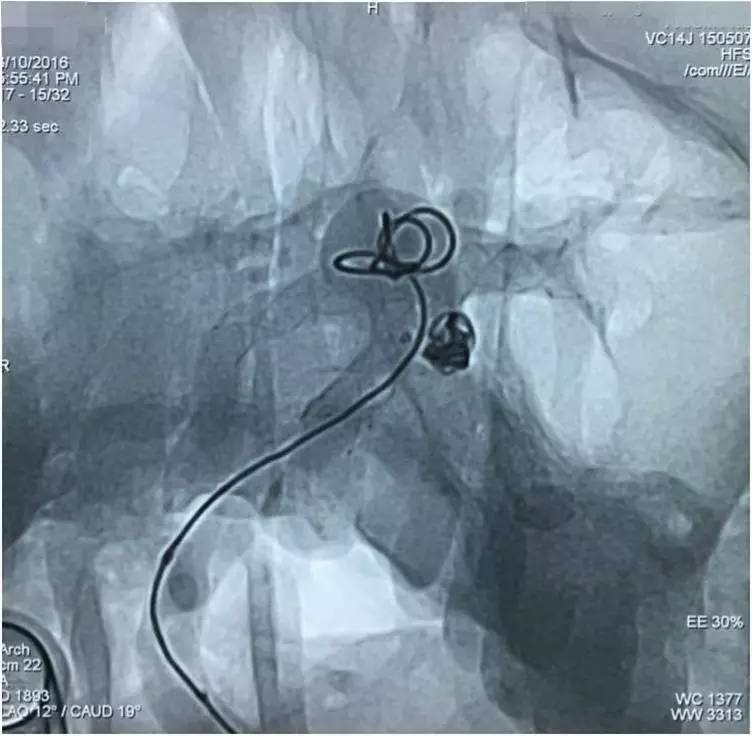

▼Headway17完成左小脑上动脉瘤的栓塞后,再经支架网眼导入右PCA,将第二枚LVIS JR 3.5*23支架跨瘤颈释放入右PCA-基底动脉,如此完成了Y型支架的释放,为基底动脉顶端动脉瘤的栓塞工程摆好了脚手架。

▼微导丝经支架内部弓背进入右PCA,Headway17微导管跟进,目的是加强第二枚支架(穿过了第一枚支架的网眼)的扩张性和贴壁性。